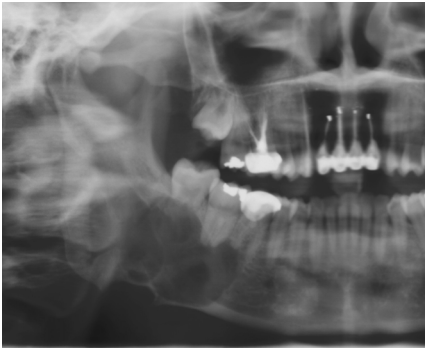

46. 下圖所示為那一種囊腫手術步驟?

(A) 刮除術(curettage) (B) 剜出術(enucleation) (C) 切開引流(incision and drainage) (D) 造袋術(marsupialization)